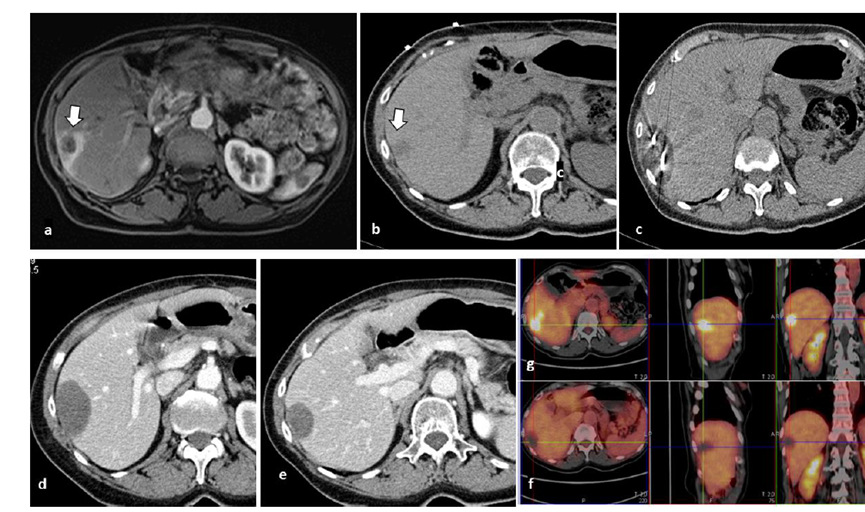

冷凍消融膽囊附近腫瘤病灶

(A)動脈期 MRI 顯示膽囊附近有外周增強病變(箭頭)。

(B)手術過程中 CT 顯示冷凍探針位于病灶內(nèi)。

(C)消融后,術后 1 個月CT 顯示完全消融(箭頭)。

(A)動脈期CT圖像顯示有一個包膜下結節(jié)(箭頭)。(B)門靜脈期CT圖像顯示病灶區(qū)(箭頭)。(C) 在手術過程中的CT顯示一個冷凍探針位于病灶內(nèi)。患者在手術及住院期間無并發(fā)癥及重大并發(fā)癥發(fā)生。隨訪時間中位數(shù)為7個月(范圍:3-12個月),隨訪期間患者無局部腫瘤進展或死亡。

(A)門靜脈期 CT 圖像顯示膽囊附近有病變(箭頭)。(C) 手術過程中CT 顯示冷凍探針位于病灶內(nèi)。(D)消融手術后 1 個月CT 顯示完全消融。